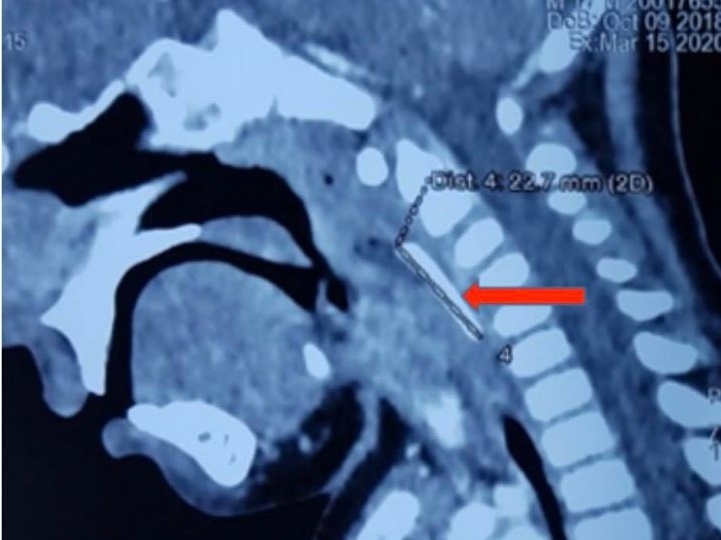

Dị vật nằm sâu trong cơ thành sau hòng, trước cột sống cổ. Ảnh: BVCC.

Tại đây, trẻ được các bác sĩ chuyên khoa Tiêu hóa nội soi để tìm dị vật nhưng không thấy. Bé 18 tháng tuổi tiếp tục được tiến hành chụp CT-scan vùng cổ, phát hiện thấy dị vật dài khoảng 2 cm nằm sâu trong thành sau họng, trước cột sống cổ. Các bác sĩ khoa Tiêu hóa và Tai mũi họng phối hợp thực hiện phẫu thuật bóc tách cơ thành sau họng lấy dị vật. Đây là thanh nhựa trắng, mảnh, dài khoảng 2 cm. Sau phẫu thuật trẻ tỉnh táo, hết khó thở, không chảy máu, nôn ói.